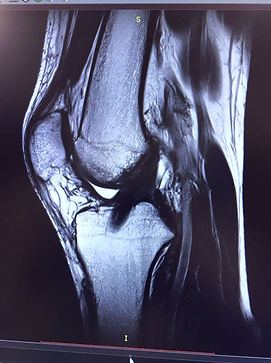

Пациент, возраст 28 лет, подвергся хирургическому вмешательству на передней крестообразной связке (ПКС) один год назад. Трансплантат (ПКС) был выполнен из сложенных втрое сухожилий полусухожильной и сдвоенной нежной мышцы.

На представленной магнитно-резонансной томограмме (МРТ) трансплантат новой передней крестообразной связки демонстрирует полное морфологическое соответствие и структурное подобие с порванной связкой, что свидетельствует о высокой степени интеграции и функциональной состоятельности трансплантата.